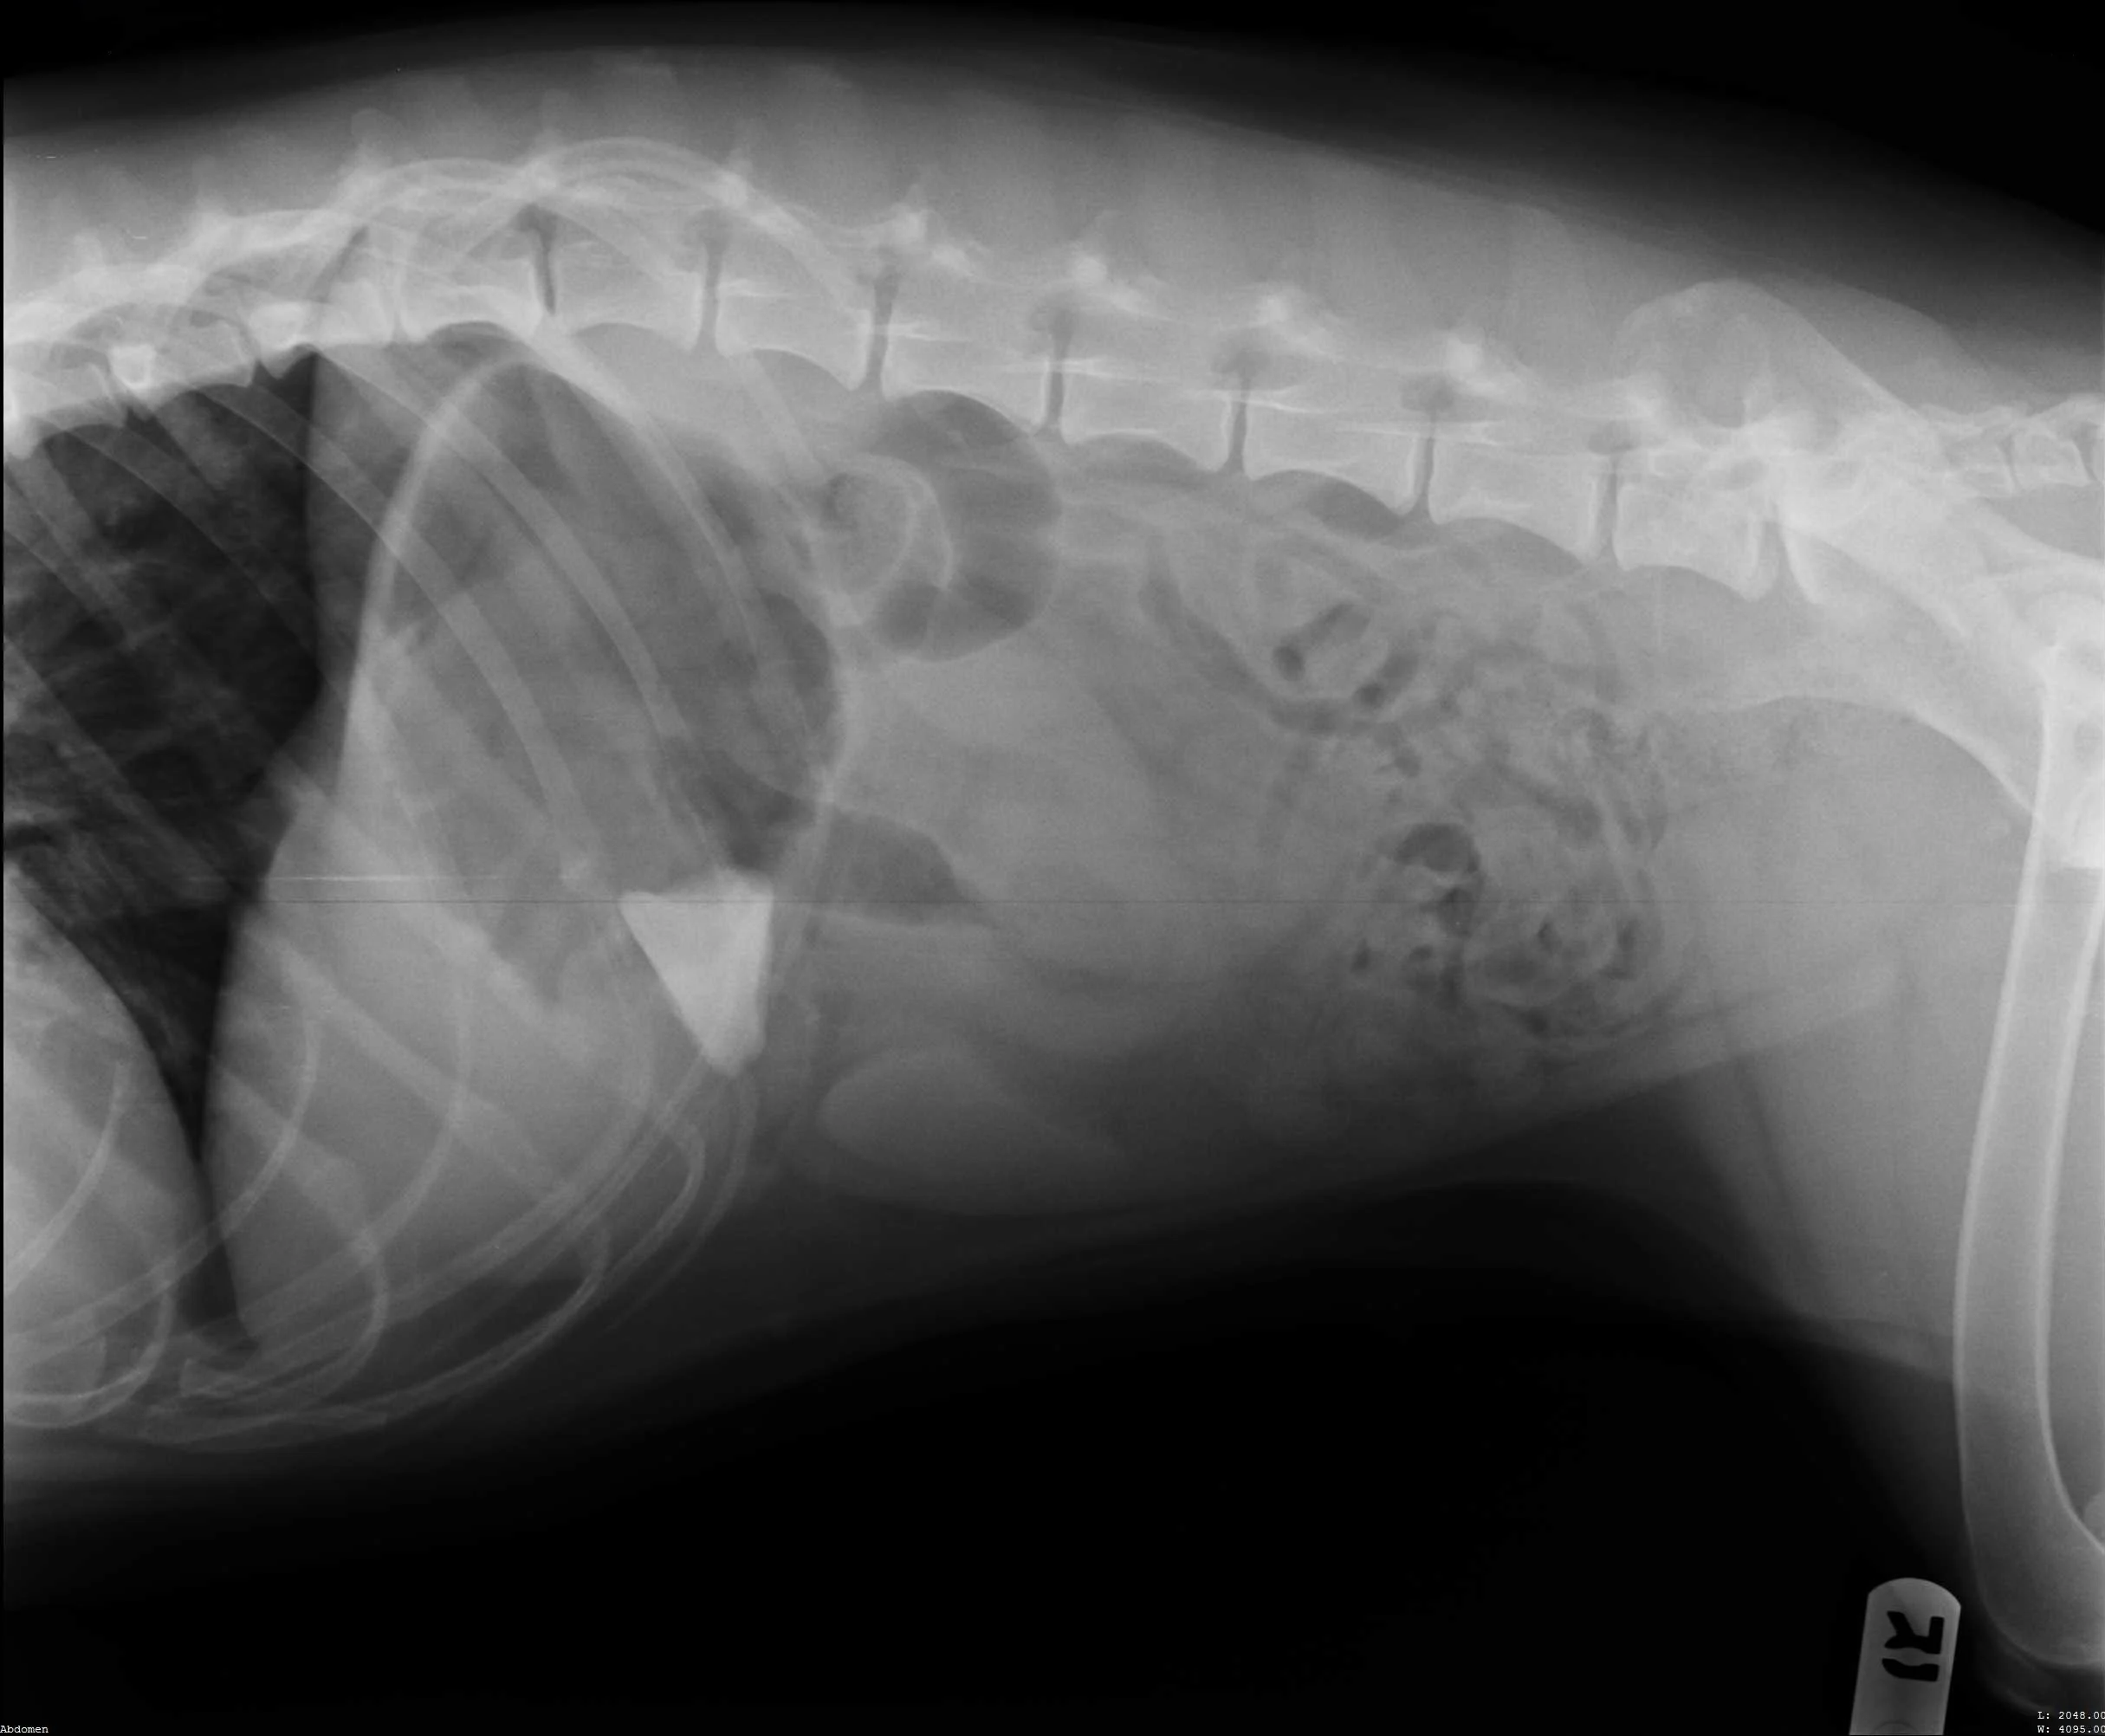

Patient’s right lateral thorax

Abdominal radiographs revealed a rock in the patient’s stomach, leading to a diagnosis of a gastric foreign body with outflow obstruction and a secondary finding of megaesophagus.

Right lateral abdomen